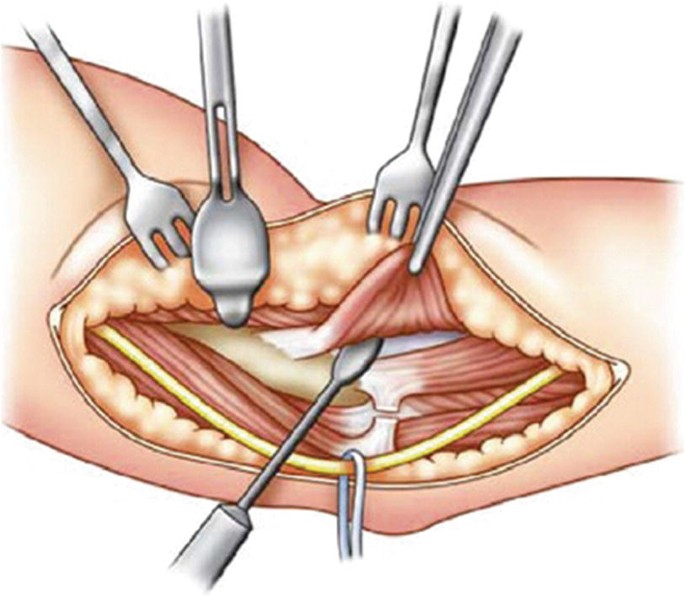

Elbow surgery is recommended for conditions such as tennis elbow, golfer’s elbow, ligament tears, chronic instability, cartilage damage, fractures, nerve compression, and post-traumatic stiffness. Using minimally invasive and muscle-sparing approaches, we help restore full motion, reduce pain, and protect long-term elbow function.

✔ Arthroscopic Elbow Surgery